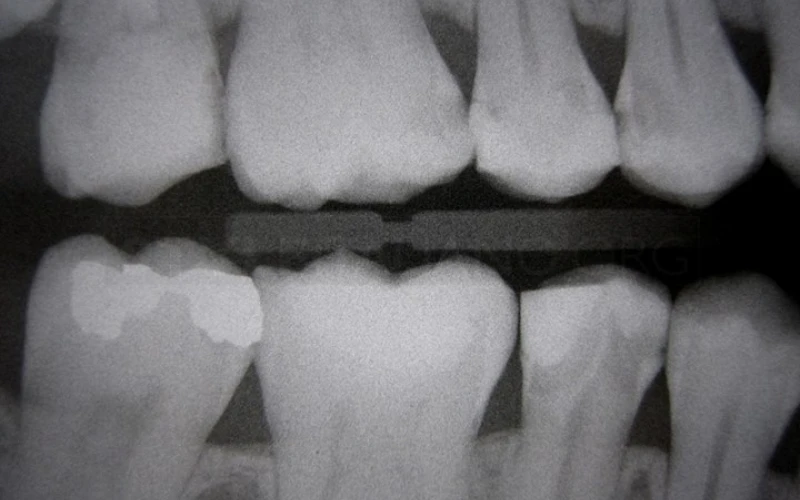

2. Phim cánh cắn cho thấy các răng nguyên nhân.

18. Phim cánh cắn sau điều trị. Tất cả các phục hình đều là composite, trực tiếp hoặc gián tiếp.